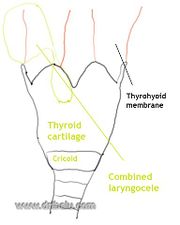

| 15:37, 22 October 2018 | Comb lcele.jpg (file) |  |

45 KB | Drtbalu | |